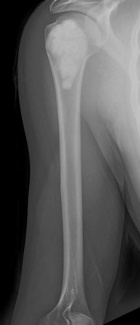

28 y/o male eight years s/p curettage and cementation for a right proximal humerus lesion found to be an aggressive enchondroma; presents with increasing R shoulder pain, worse with activity and direct pressure

PE: Healed surgical scar R shoulder, no TTP, mild edema, no LAN; FAROM, neurovascularly intact, 5/5; pain reproduced with shoulder extension and pulling